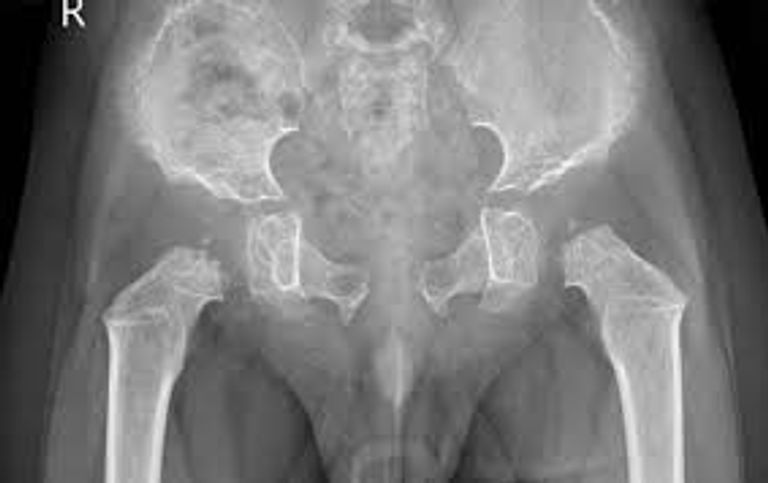

ويؤدي هذا النقص إلى تراكم المواد السكرية المعقدة في أنسجة الجسم، مسببا تشوهات هيكلية شديدة منذ الطفولة المبكرة ومشكلات متعددة في القلب والعينين والمفاصل، بينما يبقى الإدراك العقلي غالبا سليما.

الدراسة التي حصلت العين الإخبارية على نسخة منها، وتنشرها دورية "مولكيولار جينيتكس آند ميتابوليزم ريبورتس" هذا الشهر، راقبت 33 طفلا من 26 عائلة عراقية مختلفة، وسجلت أن أكثر من 90% منهم ينحدرون من أسر متزوجة بين الأقارب، ما يعكس التحديات الوراثية في المجتمع العراقي. وأكدت النتائج وجود تأخر كبير في النمو، تشوهات هيكلية عامة، عتامة القرنية، أمراض صمامات القلب، وفقدان السمع لدى أغلب الأطفال.